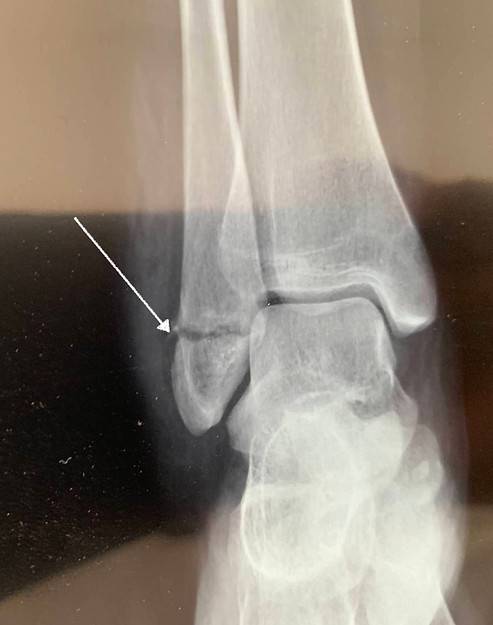

Explication de la fracture de cheville

Après le traumatisme, la cheville gonfle et est déformée. Elle sera prise en charge initialement par un urgentiste qui va réaxer la cheville et l'immobiliser dans un plâtre afin d'attendre la chirurgie. C'est un geste qui peut être douloureux mais qui apaise immédiatement la douleur une fois la cheville immobilisée. Une radio sera faite pour vérifier l'état de la cheville dans le plâtre.

Quel traitement chirurgical pour une fracture de la cheville ?

Une incision est faite en face de l'os fracturé. Il est remis en position anatomique et une plaque ou des vis stabilisent la fracture. La peau est recousue et le pansement est enfermé dans le plâtre ou dans une botte de marche. Des radio peuvent être faite à travers le plâtre pour vérifier que la fracture ne bouge pas. Vous marcherez avec des béquilles sans poser le pied au sol, ou sur votre botte de marche. Le plâtre est enlevé après 6 semaines. La kinésithérapie commencera et durera environ 3 mois. Les plaques resteront en place à moins d'une gêne ou une complication.